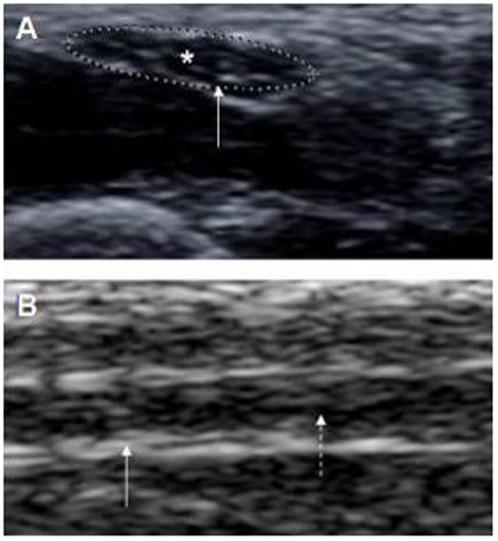

Leprosy is the most common treatable peripheral nerve disorder worldwide with periods of acute neuritis leading to functional impairment of limbs, ulcer formation and stigmatizing deformities. Since the hallmarks of leprosy are nerve enlargement and inflammation, we used high-resolution sonography (US) and color Doppler (CD) imaging to demonstrate nerve enlargement and inflammation.

METHODOLOGY/PRINCIPAL FINDINGS: [corrected] We performed bilateral US of the ulnar (UN), median (MN), lateral popliteal (LP) and posterior tibial (PT) nerves in 20 leprosy patients and compared this with the clinical findings in these patients and with the sonographic findings in 30 healthy Indian controls. The nerves were significantly thicker in the leprosy patients as compared to healthy controls (p<0.0001 for each nerve). The two patients without nerve enlargements did not have a type 1 or type 2 reaction or signs of neuritis. The kappa for clinical palpation and nerve enlargement by sonography was 0.30 for all examined nerves (0.32 for UN, 0.41 for PN and 0.13 for LP). Increased neural vascularity by CD imaging was present in 39 of 152 examined nerves (26%). Increased vascularity was observed in multiple nerves in 6 of 12 patients with type 1 reaction and in 3 of 4 patients with type 2 reaction. Significant correlation was observed between clinical parameters of grade of thickening, sensory loss and muscle weakness and US abnormalities of nerve echotexture, endoneural flow and cross-sectional area (p<0.001).

CONCLUSIONS/SIGNIFICANCE: We conclude that clinical examination of enlarged nerves in leprosy patients is subjective and inaccurate, whereas sonography provides an objective measure of nerve damage by showing increased vascularity, distorted echotexture and enlargement. This damage is sonographically more extensive and includes more nerves than clinically expected.